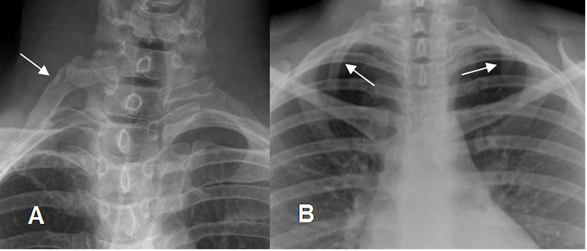

COSTILLA CERVICAL:

Corresponde a una costilla supernumeraria, generalmente articulada con la apófisis transversa de C7. (4). (Fig 21).

En la mayoría de los casos la alteración es asintomática, aunque puede ocasionar síndrome de la abertura torácica superior, con compresión de los vasos subclavios. (4).

Fig 21. Costilla cervical.

A y B: Rx AP. Costillas supernumerarias, en relación con la apófisis transversa de C7. En la malformación es bilateral.